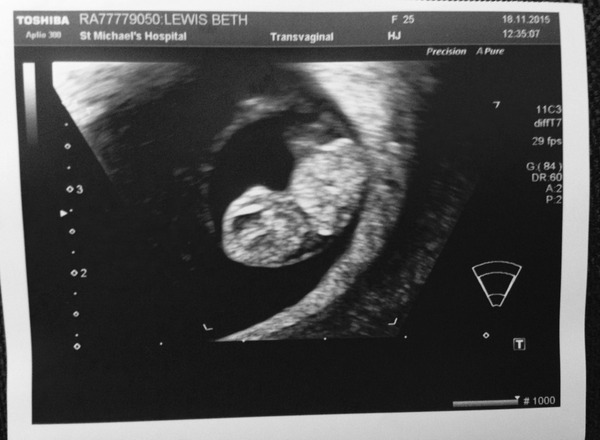

mrslewis2015 · 18/11/2015 13:53

What a gorgeous scan nerharg!! You must be delighted! Enjoy telling everyone!

Just got home from our scan, saw our gorgeous little bean with a perfect little heartbeat!! And very sweet little legs! What a moment, my DH was very happy as am I!

I have a 4cm cyst on my right ovary too, but they say they aren't worried, hopefully it will sort itself out!

The photo isn't as clear as the screen but it's lovely to have a pic!

Oh and they put me at 8+5 rather than 8+1! Yay!